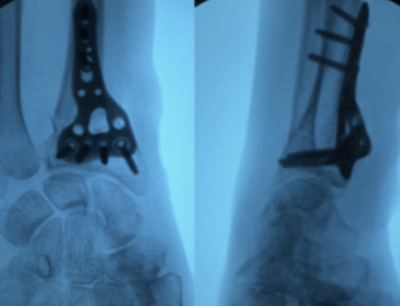

Fixation avec plaques

Pour les fractures instables ou déplacées, même si les os sont repositionnés et qu’un plâtre est mis en place ensuite, les fragments osseux ont tendance à re-bouger secondairement ou à adopter une mauvaise position avant de consolider. Ces fractures nécessitent donc une intervention chirurgicale afin de rétablir et maintenir l’alignement des os en les fixant avec du matériel (plaque).

Le chirurgien peut dans certain cas s’aider d’une caméra (arthroscopie) pour visualiser l’articulation de l’intérieur si besoin.